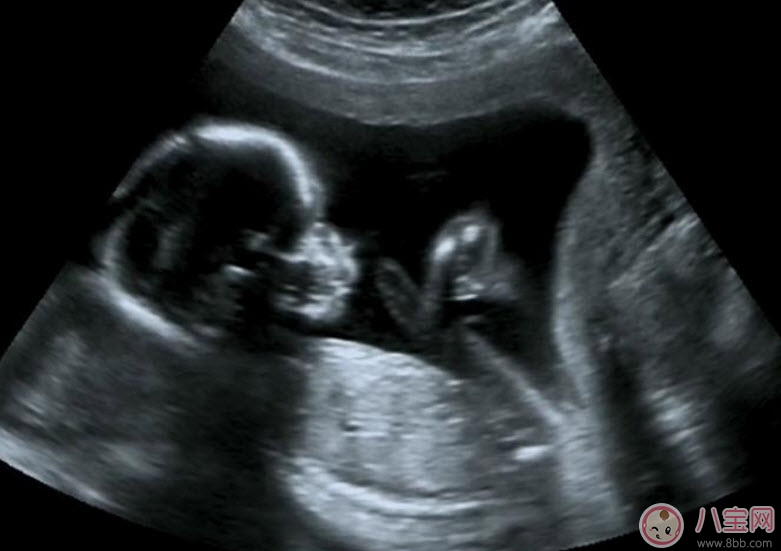

5、觀察胎兒生理活動情況

B超能夠直觀胎兒在母體內(nèi)的活動狀況,諸如呼吸情況、胎兒的運動、整個身體大的運動、肢體的運動、胎兒的吞咽動作等等,可以一覽無余。之外,通過觀察胎兒的張力是否良好,可以判斷胎兒在宮內(nèi)是否缺氧或者受到損害,準確預(yù)報胎兒安危。